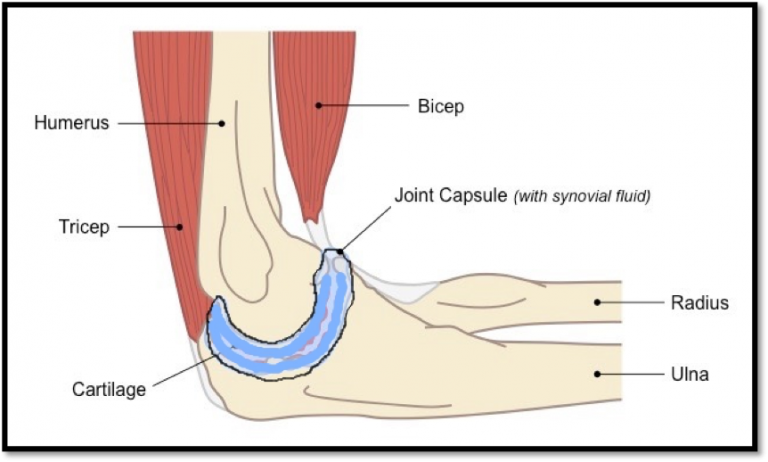

The elbow joint is formed by 3 bones- one arm-bone (Humerus) and two forearm bones (Radius, ulna). Like other joints the two bones are connected by ligaments and surrounded by muscles.

This condition is seen in young patients between the ages of 20-45 years. The inner lining of the elbow joint starts to abnormally produce excess cartilage and bone like tissue. Normally this lining produces a lubricating fluid. These cartilage-like loose bodies within the elbow joint initially irritate and then abrade the cartilage of the joint. Cartilage is the protective covering over the joint surface. Loss of this protective covering leads to arthritis and damage of the elbow joint.